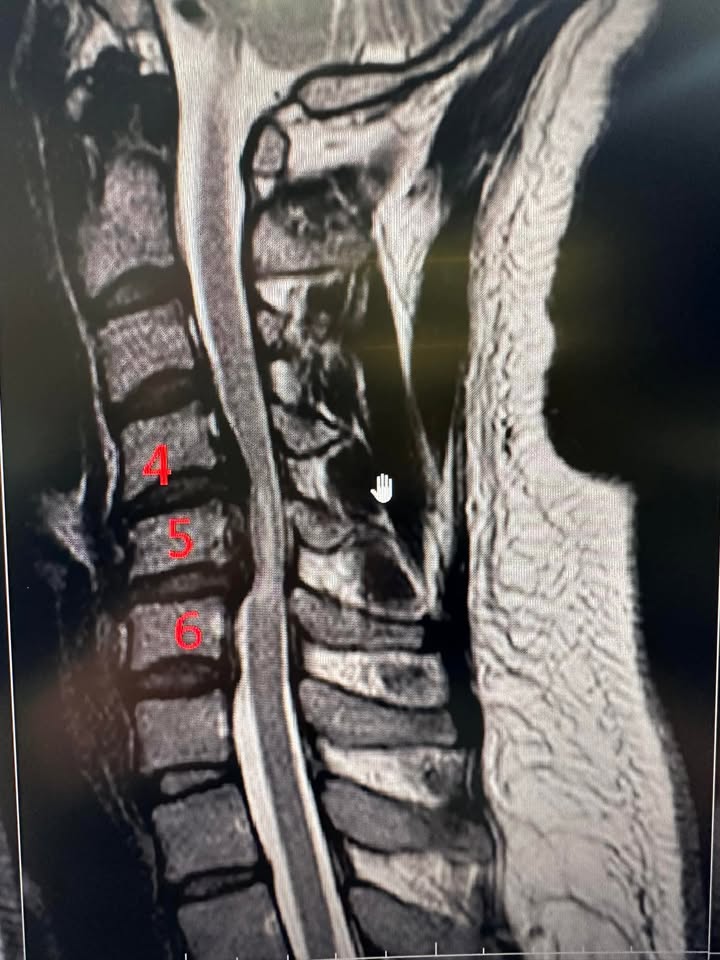

Cervical Spine Treatment Cases 精彩回顧 椎間盤突出合併狹窄醫案 2023.08.30 2023.09.01 2023.09.02 神經根型頸椎病醫案 2023.09.03 2023.09.04 頸椎反弓合併神經根卡壓醫案 2023.09.05 2023.09.07 2023.09.13 脊髓型頸椎病醫案 2023.09.13 2023.09.14 2023.09.16 2023.09.18 2023.09.19 2023.09.20 中重度椎孔狹窄醫案 2023.09.20 ← 上一頁 13 14 15 16 17 下一頁 →